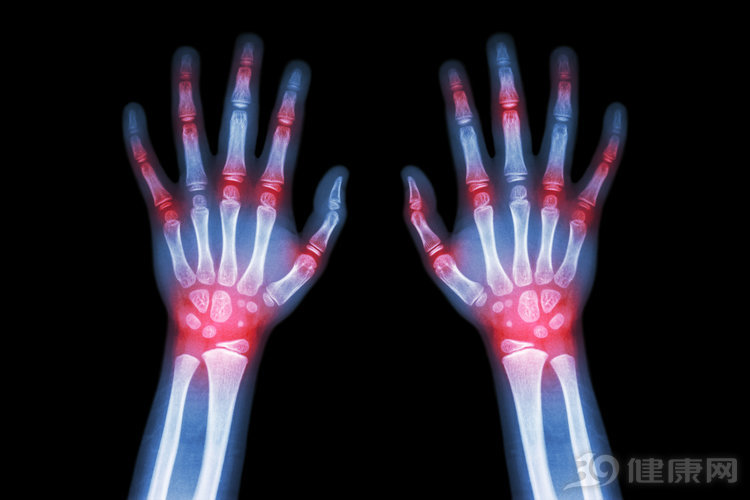

临床上比较常用于治疗痛风的秋水仙碱,目前医学界对这个药的争议还是挺大的,我们应该如何正确使用秋水仙碱,是痛风患者必须要了解的重要话题。该药应附带药物指南。痛风患者请仔细阅读并遵循这些说明。如果您有任何疑问,请咨询您的医生。

对于痛风患者来说,不同的服用需求,其需要预防的内容也是不一样的,现在就为大家分开来进行讲解下。

1.当痛风轻微,不常见且不复杂时,可以通过改变饮食和改变生活方式来治疗。当痛风发作频繁时,常常会发生尿酸肾结石,存在痛风石,药物通常用于降低尿酸血液水平。除了秋水仙素,其他的治疗方法也是比较有效的。

了解过痛风的人都应该知道,此病发作的时候,疼痛异常,而痛风的发生发展,与人们的饮食结构密切相关,所以我们要在日常生活中多加以注意。